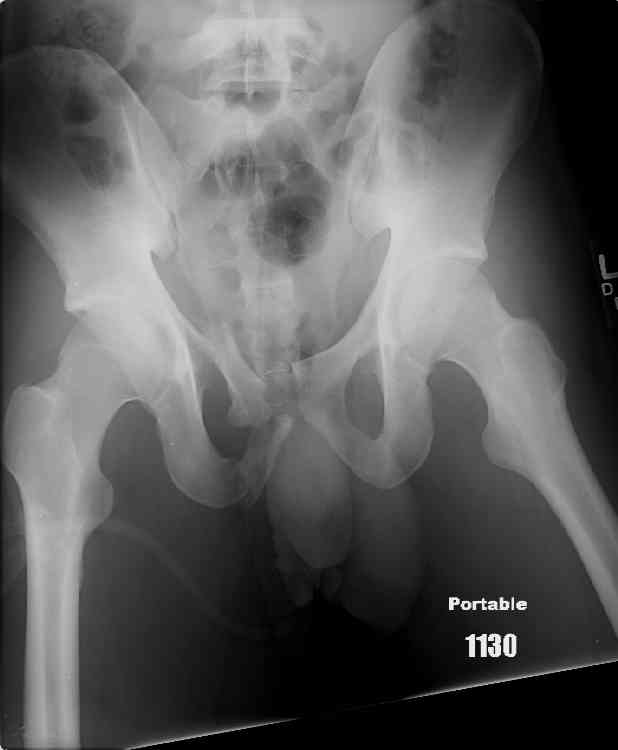

this is a healthy 22yo male. peds vs auto.

no other injuries. has anyone treated these non-operatively? thanks.